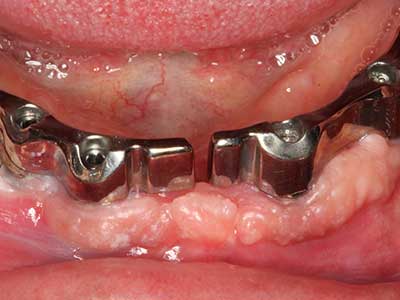

For removal of an implant, a vestibular bone cover that is replaced after removal of the implant screw can be prepared to retain the contour of the alveolar ridge.